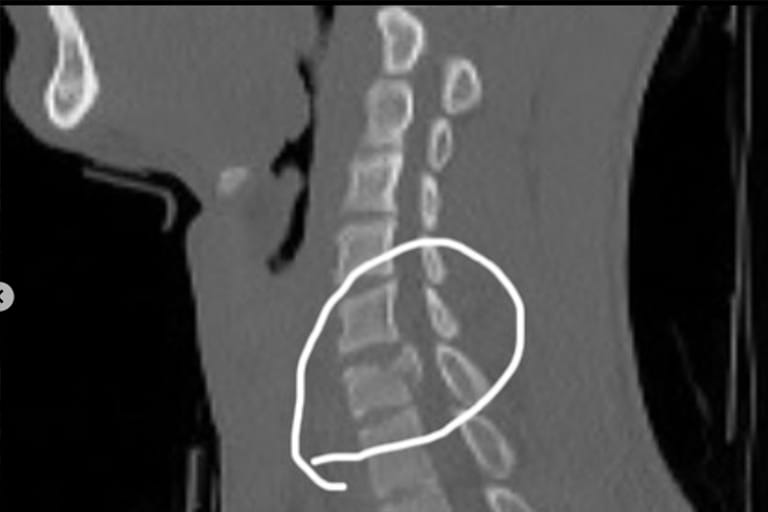

Im zweiten Youngsters-Rennen von Bitsch am vergangenen Wochenende zog er den Holeshot und wurde Dritter. "Ich konnte zeigen, dass meine körperliche Fitness und mein Fahren wieder auf einem top Stand sind", erklärte der 20-Jährige. Im dritten Lauf ereignete sich das Drama. Jan erklärt: "Ich ging auf Rang 7 in die erste Kurve und in den Whoops fuhr mir ein anderer Fahrer ins Hinterrad, sodass ich stürzte. Hinter mir sind dann gleich mehrere Fahrer über meinen Nacken und Rücken gefahren. Ich habe sofort gemerkt, dass sich alles versteift. Zuerst konnte ich nicht einmal aufstehen. Nach kurzer Zeit ging das wieder, aber Nacken und Rücken haben sich nicht gut angefühlt. Ich bin in Frankreich ins Krankenhaus gebracht worden, wo ein Bruch des Halswirbels C6 diagnostiziert wurde. Am selben Abend wurde ich nach Saarbrücken verlegt, wo ich am Montag operiert wurde." Der Wirbel wurde so stark beschädigt, dass sowohl der Wirbelkörper als auch die Bandscheiben operativ entfernt werden mussten. "Der Halswirbel wurde komplett entfernt und durch einen künstlichen Wirbelkörper ersetzt", erklärt Krug. "Die Bandscheiben über und unter dem Wirbel mussten ebenfalls ersetzt werden."

Die Operation verlief gut. Jan hat keine Lähmungserscheinungen. Wie sich dieser Eingriff künftig auf seine Beweglichkeit auswirken wird, scheint im Moment noch unklar zu sein. Krug zeigt sich aber vorsichtig optimistisch: "Stand jetzt bin ich guter Dinge, dass alles wieder in Ordnung kommt. Wie lange es dauert, wird sich herausstellen, aber ich freue mich auf nächstes Jahr, mit vollem Einsatz fahren zu können und hoffe auf eine verletzungsfreie Saison."